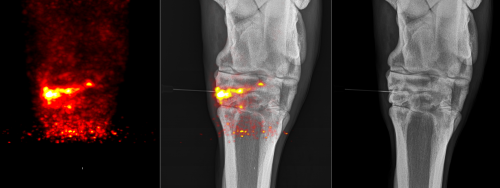

Another example of a case scanned with the MILEPET at UC Davis was an American Quarter Horse with lameness localized to the hock but no definitive answers on X-rays and ultrasound. This mare was the first to have standing scans of the hock performed with the MILEPET. The scans were successful and demonstrated early joint disease that was responsible for the pain. The PET results helped target the exact area of the joint to inject.

The image to the left is one of the obtained PET images. The yellow area indicates abnormal bone. When overlaid with the X-ray (middle image), it shows that the injury is centered on one of the small joints of the hock, despite minimal changes on the X-ray (image on the right). With this information, the abnormal joint was injected with corticosteroids to alleviate the pain.